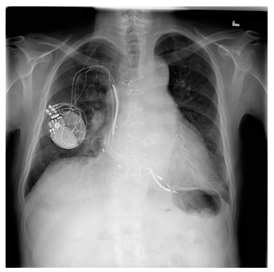

Breast-MRI-NACT-Pilot is an MRI-type image database, collecting breast medical images of 64 patients. Some samples are shown in Figure 12a.

Figure 12.

Sampled images in the tested benchmark databases: (a) Breast-MRI-NACT-Pilot (breast), (b) ACRIN-DSC-MR-Brain (brain), (c) NIH (chest), (d) Lung-PET-CT-Dx (lung), (e) Prostate-MRI (prostate), and (f) Other grayscale standard images.

ANIH is an X-ray type image database collecting chest medical images. Some samples are shown in Figure 12c.